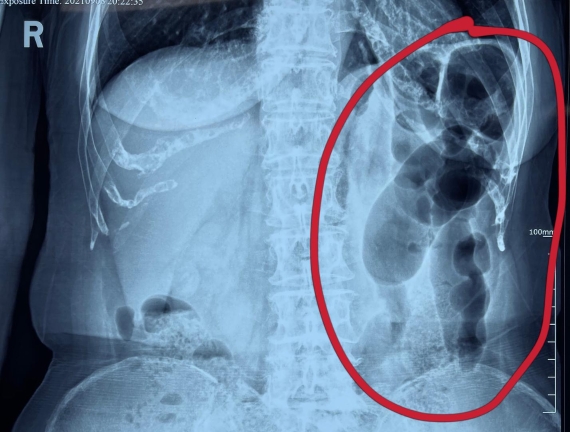

據(jù)省醫(yī)院消化病院消化二科姜子曄醫(yī)生介紹,韓大娘今年已經73歲,家住哈爾濱市,一周前開始腹脹腹痛,有較為明顯的左側腹部疼痛,疼痛劇烈時會出現(xiàn)左側腹部鼓包情況,排氣排便后有所好轉。韓大娘家人見狀將其送到了黑龍江省醫(yī)院,門診檢查腹部平片提示為左側腹部積氣,口服全消化動力藥及通便治療后腹痛腹脹有所緩解,入院前再次突發(fā)左側腹痛加重伴有明顯腹脹,急診隨后以“腹痛腹脹原因待查”將韓大娘收入到消化病院消化二科。

姜子曄醫(yī)生熱情接待了韓大娘,為其進行了仔細查體,除了左側腹部壓痛并未見明顯異常,對癥給予灌腸后,韓大娘的腹脹有所緩解,第二天姜子曄醫(yī)生為韓女士進行了胃腸鏡檢查,也未見明顯異常。但此時韓大娘腹部平片結腸腸管擴張仍然很嚴重,腹痛腹痛也沒緩解,到底什么原因呢?消化二科主任陸以霞在查房時建議繼續(xù)給予韓大娘口服全消化動力藥,必要時灌腸治療,同時陸以霞主任在追問病史查體時發(fā)現(xiàn)韓大娘左下腹紅色皮疹和小水泡,反復抓撓腹部皮膚部分已結痂,高度懷疑為帶狀皰疹。